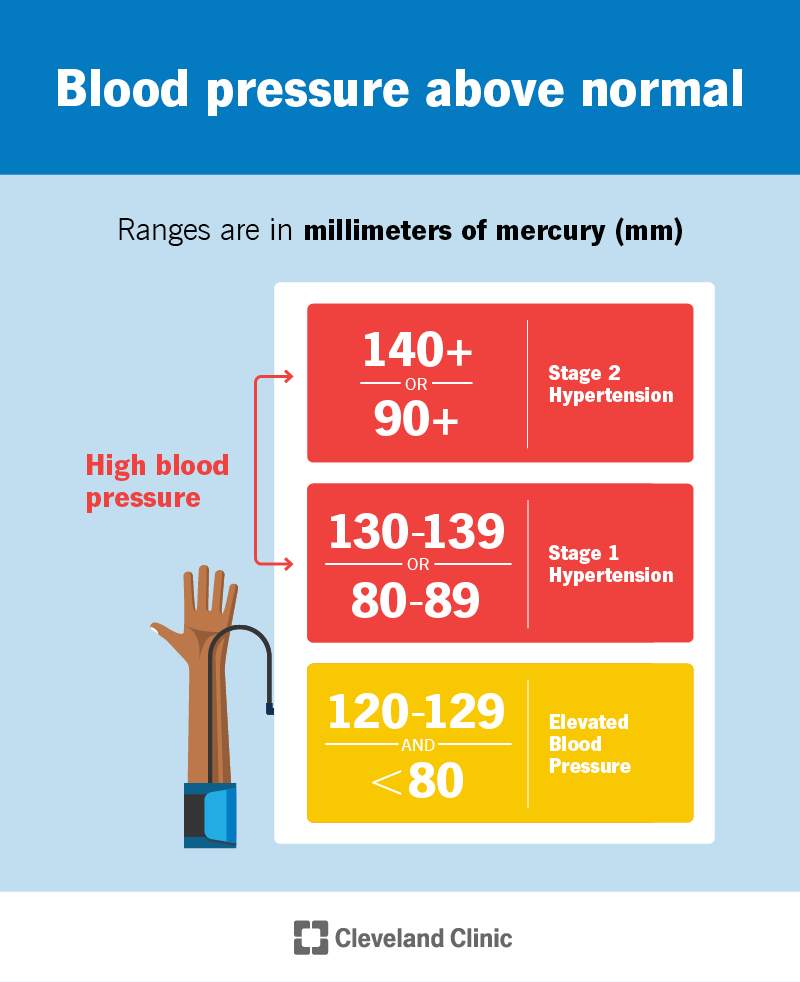

Does Blood Pressure Increase With Heart Failure

Does Blood Pressure Increase With Heart Failure

https://my.clevelandclinic.org/-/scassets/images/org/health/articles/4314-high-blood-pressure.ashx

What To Know About High Blood Pressure As You Age National Institute

High Blood Pressure Hypertension Texas Heart Institute

Hypertension Types Stages Causes Symptoms Treatments